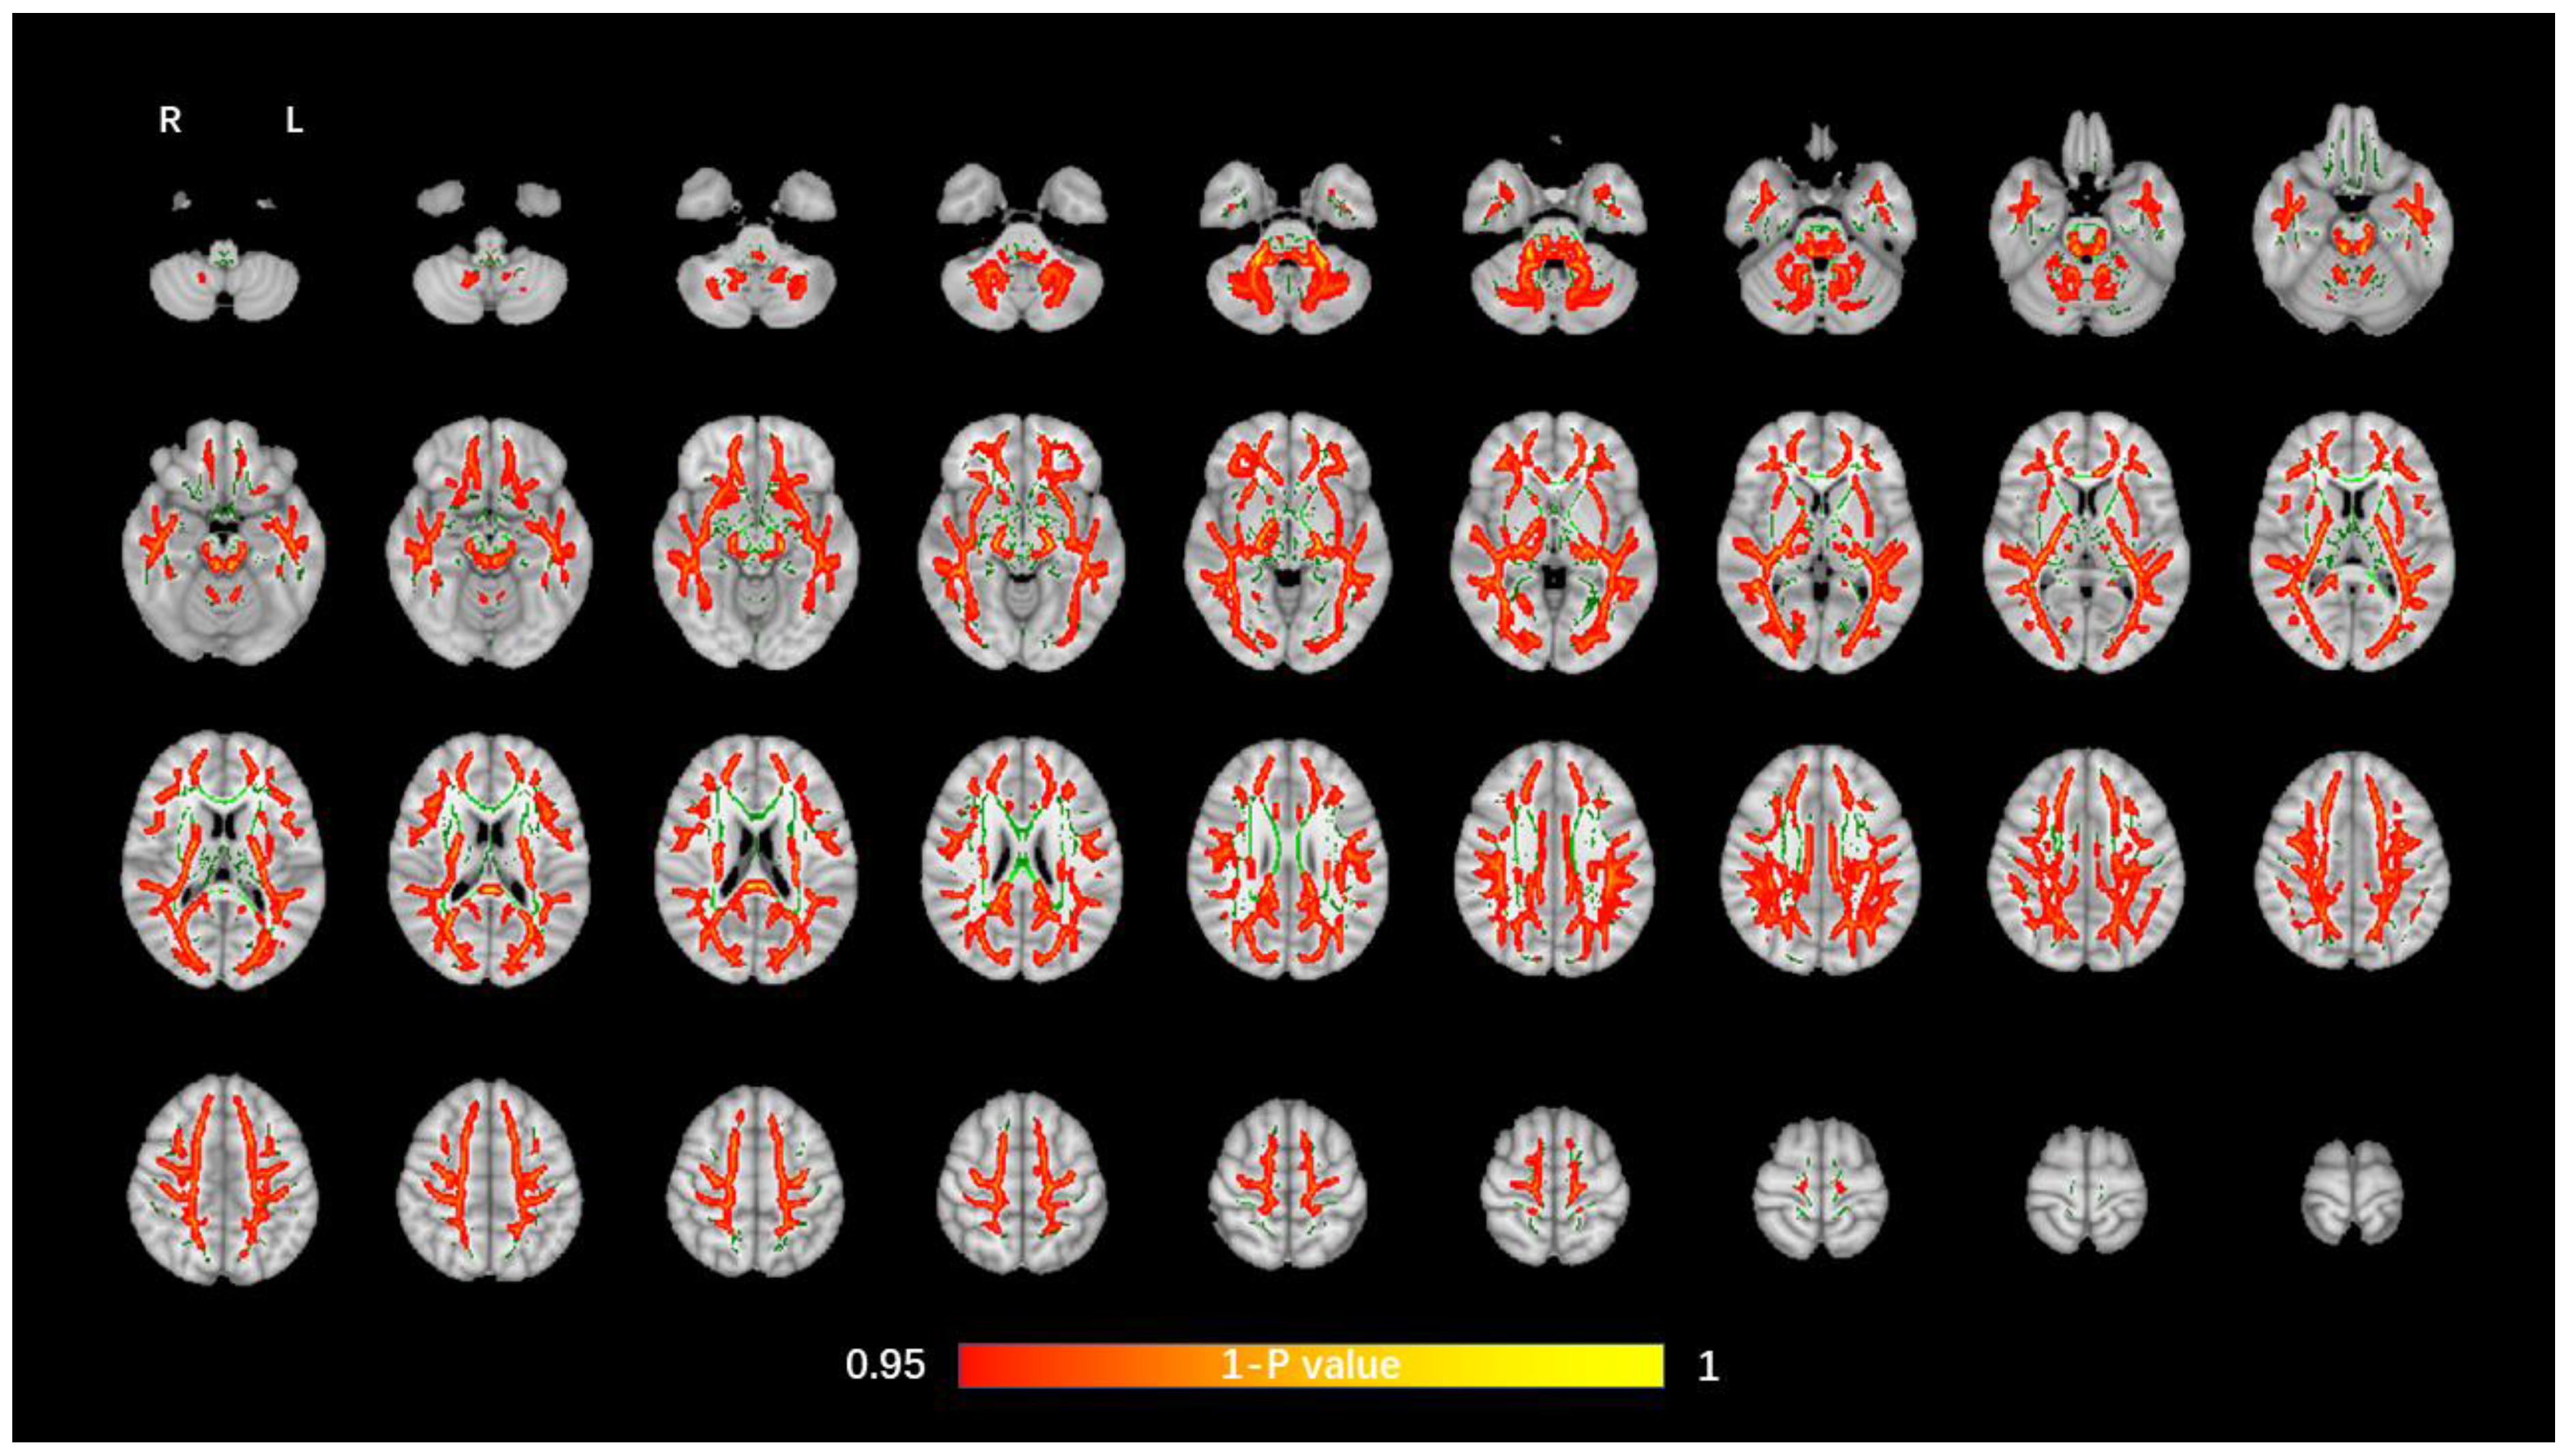

The average FA WM skeleton of all subjects was constructed in TBSS analyses, as shown by the green line in Figure 1, Figure 2, Figure 3 and Figure 4. An analysis of variance of voxel level was carried out on the WM skeleton, and the differences among the three groups were compared. p < 0.05 after FWE correction based on TFCE was statistically significant. Statistically significant areas were expanded to better show the position of WM fiber bundles, as shown in the red part in Figure 1, Figure 2, Figure 3 and Figure 4. The statistical results showed that the DTI indexes of most fiber bundles were statistically significant. There was a significant statistical difference in the FA, MD, AD, and RD values of the FMI, FMA, IFOF, SLF, ILF, ATR and corticospinal tract (CCT) among the three groups (p < 0.05; Figure 1, Figure 2, Figure 3 and Figure 4).

Figure 2.

Voxel-wise TBSS analysis results of MD images among the WML-VCIND, WML-VaD, and HC groups. Green represents the mean WM skeleton of all subjects. Red-yellow (thickened for better visibility) represents regions with a significant F-test statistical difference (p < 0.05, TFCE-based FWE-corrected). TBSS, tract-based spatial statistics; MD, mean diffusivity.